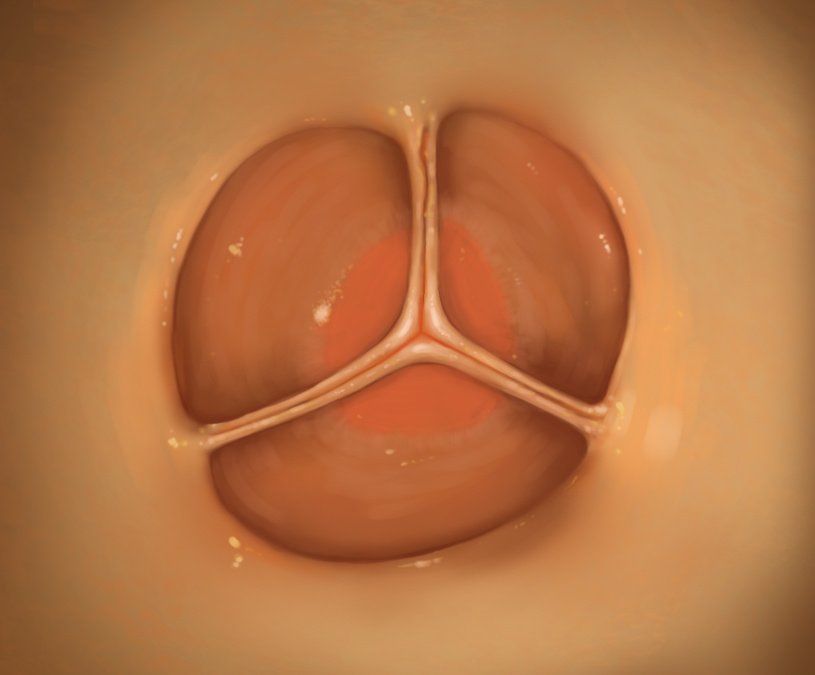

Early concept sketches of the the heart